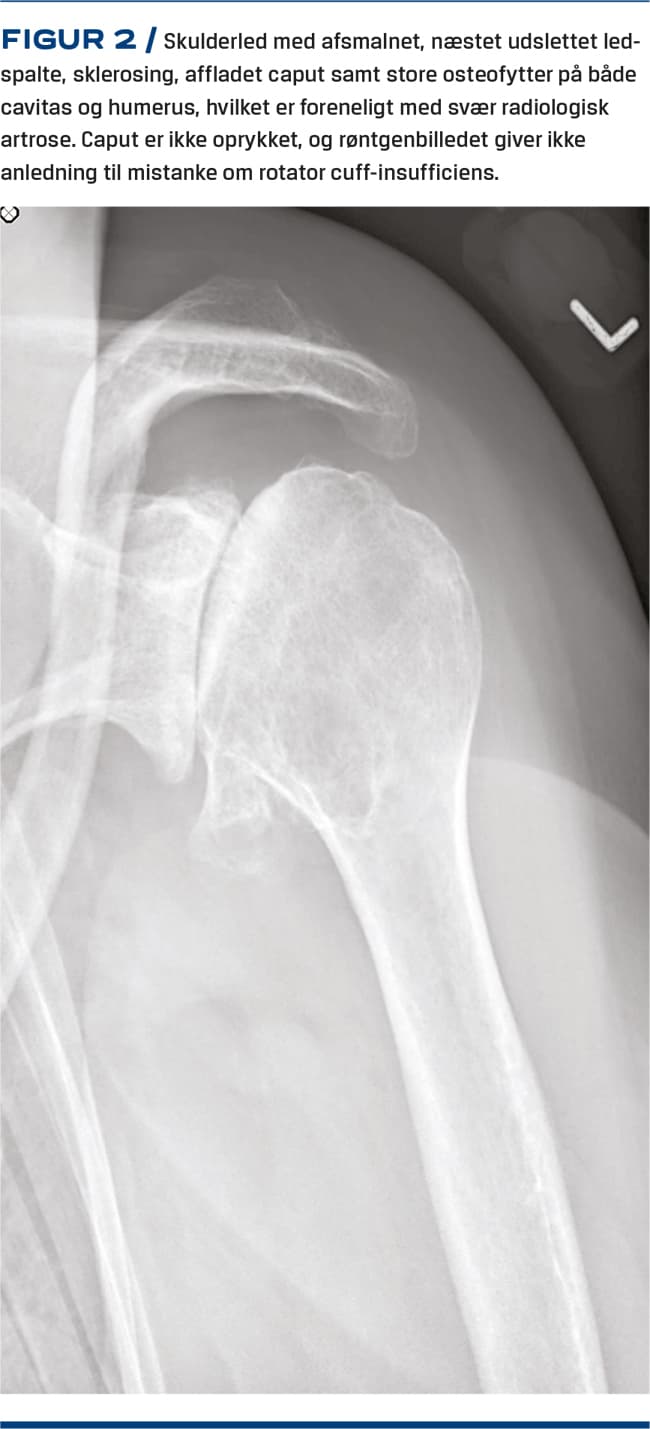

Objektivt kan der være nedsat bevægelighed og skurren. Rotator cuff-funktionen vurderes på baggrund af muskelatrofi og nedsat styrke (Figur 2).

RADIOLOGI

Før andre radiologiske undersøgelser er det væsentligt, at man starter med konventionel røntgen. Det er en prisbillig og sikker undersøgelse, der ofte er tilstrækkelig til diagnosticering af artrosen. De radiologiske fund består af reduceret ledspalte, osteofytter, knoglecyster og evt. ledmus. Undersøgelsen bruges også differentialdiagnostisk ved at påvise artritis, tumorer og tegn til ustabilitet [13-15].